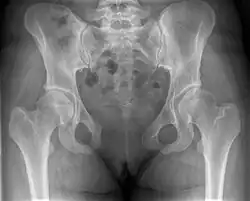

Внешний вид лобкового симфиза таза